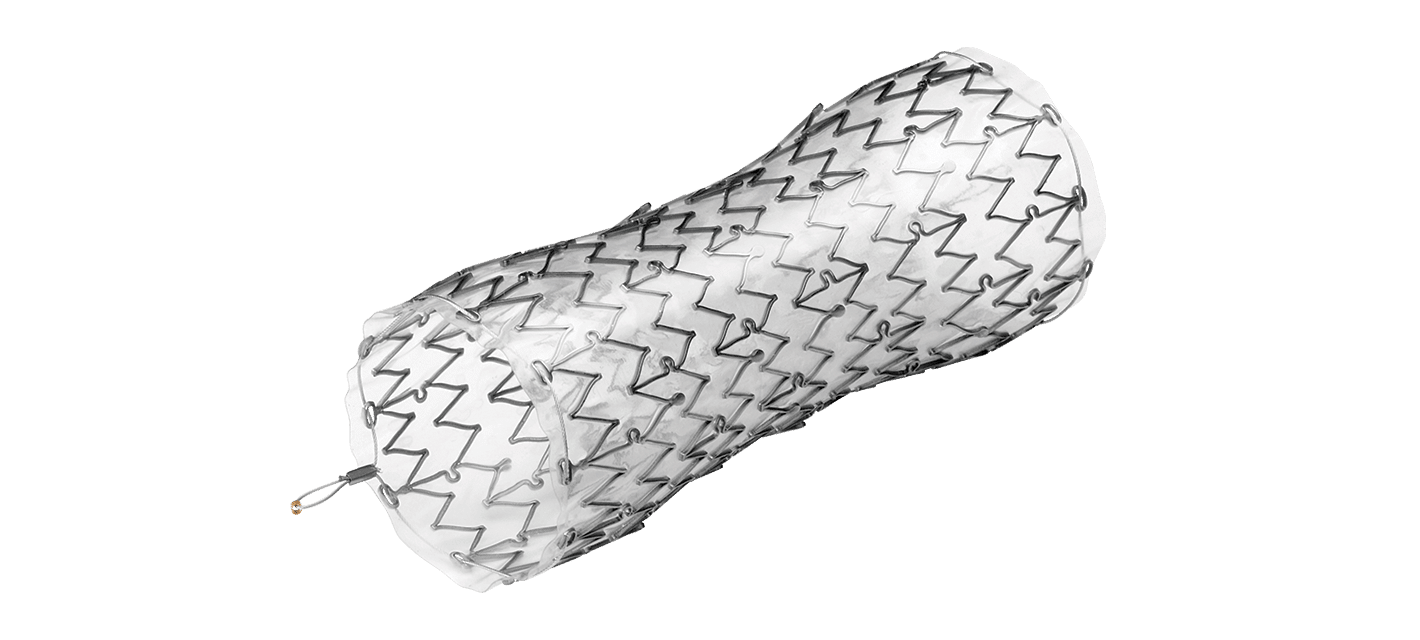

AORTIC ANEURYSM

The aorta runs from the heart through the center of the chest and abdomen. It’s the main blood vessel that brings blood to the abdomen, pelvis, and legs. An abdominal aortic aneurysm (AAA) is a life-threatening condition that occurs when the vessel enlarges, putting it at risk of bursting. Men are 4-15 times more likely to develop an AAA than women

Learn more about AAA. To learn more about our packs, wires, and other cardiac products, please visit our Merit Vascular page.

MERIT PRODUCTS